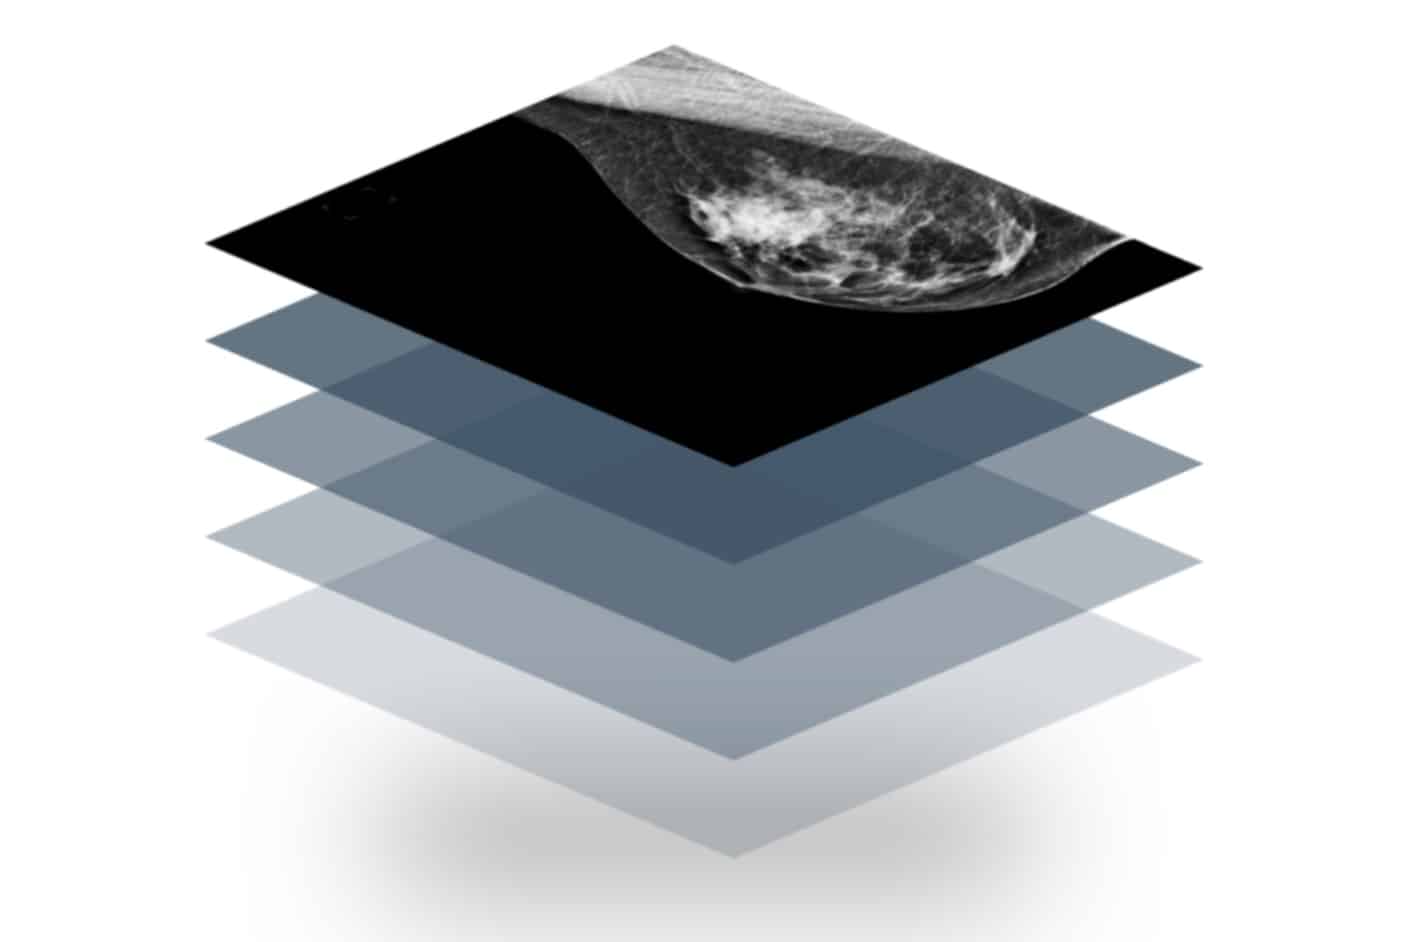

Volpara’s FDA-cleared TruDensity™ algorithm powers Scorecard, a breast density assessment software that delivers consistent, volumetric insights. It provides clinicians with consistent, objective data to support earlier cancer detection and supplemental imaging recommendations.

As the only breast density assessment software validated for use with Tyrer-Cuzick v8 (TC8), it provides precise data to support lifetime breast cancer risk assessment to help identify patients who may need additional imaging or preventive measures.